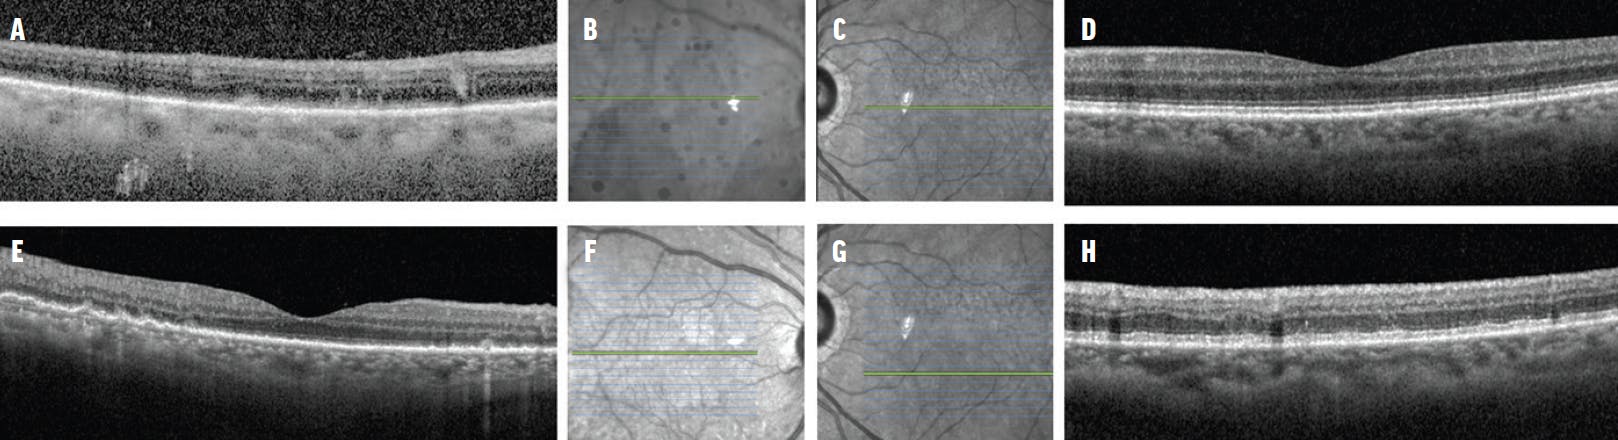

<p>Figure 2. OCT of the right eye on presentation showed image degradation secondary to vitreous debris, subretinal deposits with possible retinal pigment epithelium thickening, and pachychoroid (A). The near-infrared image with the green cut corresponded to the OCT slab seen in panel A (B). The near-infrared image of the left eye with the green cut corresponded to the OCT slab seen in panel D (C). OCT of the left eye on presentation appeared normal (D). OCT and near-infrared imaging 19 days later showed further changes (E-H).</p>

Figure 2. OCT of the right eye on presentation showed image degradation secondary to vitreous debris, subretinal deposits with possible retinal pigment epithelium thickening, and pachychoroid (A). The near-infrared image with the green cut corresponded to the OCT slab seen in panel A (B). The near-infrared image of the left eye with the green cut corresponded to the OCT slab seen in panel D (C). OCT of the left eye on presentation appeared normal (D). OCT and near-infrared imaging 19 days later showed further changes (E-H).